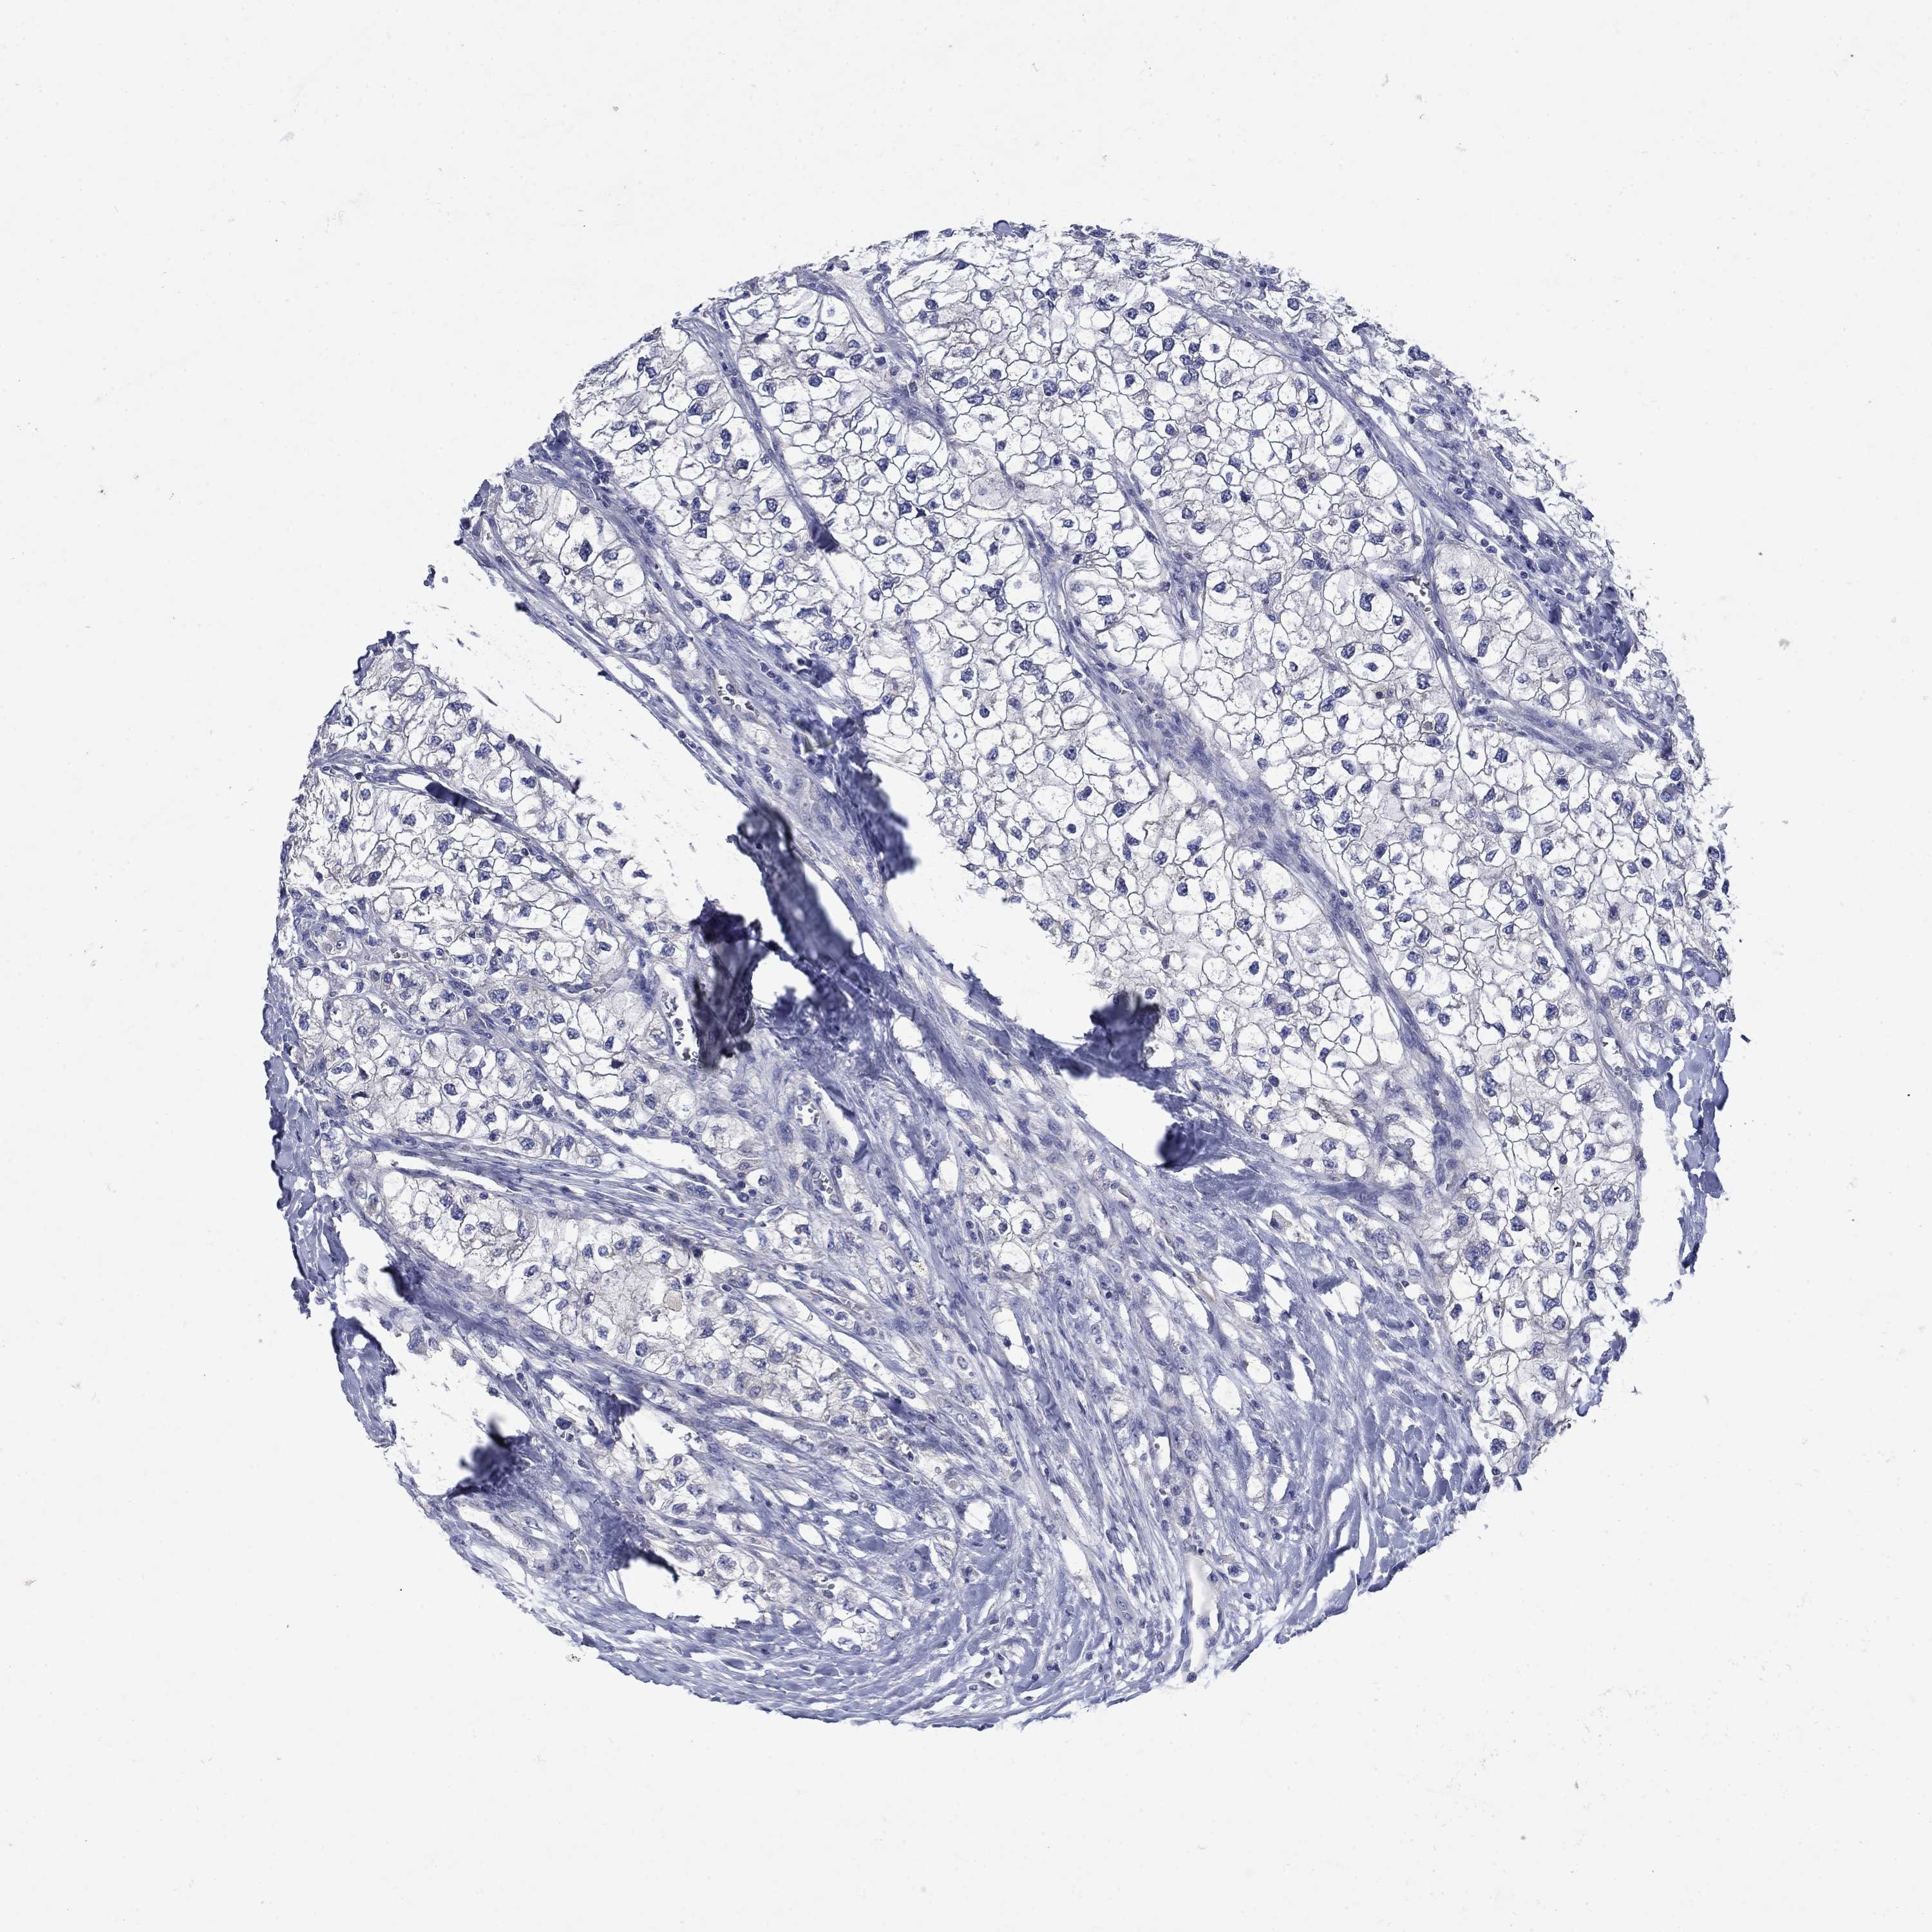

Renal cancer

Kidney renal papillary cell carcinoma